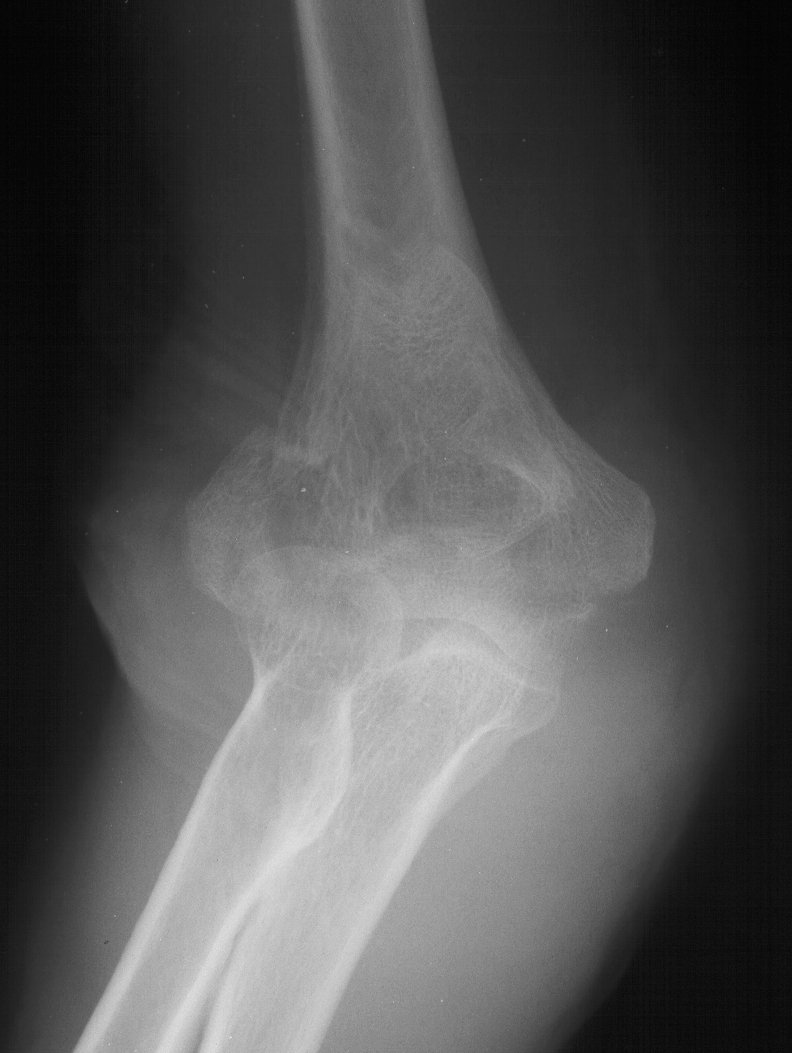

Fracture Distal Humerus